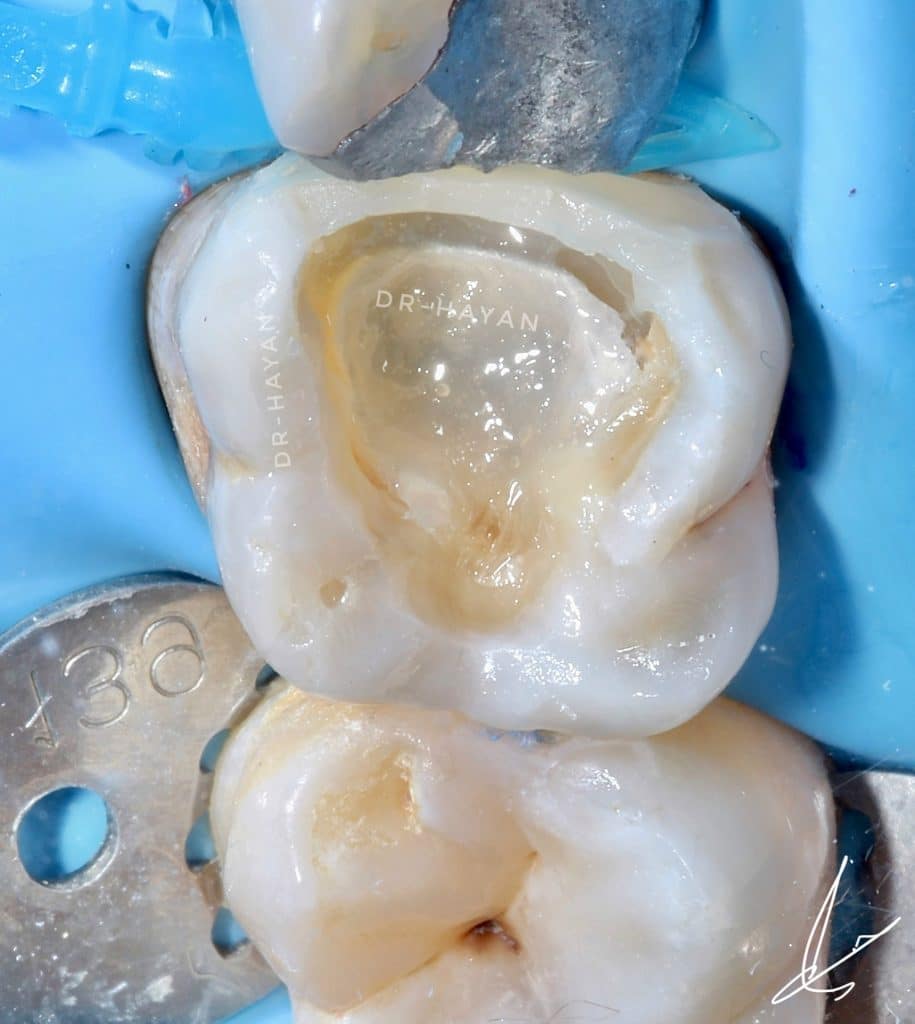

Initial view : 27 years old man suffered from sharp pain related to upper posterior area

After deep marginal acquisition ✅

Bonding ✅

Resin coating ✅

Decouple with time✅

ready for DME and class II

Before finishing

After finishing and polishing

Lateral view

The homogenization of marginal acquisition, DME and mesial wall bulding up

After rubber dam removal and extra polishing

Most important step for hermetic contact